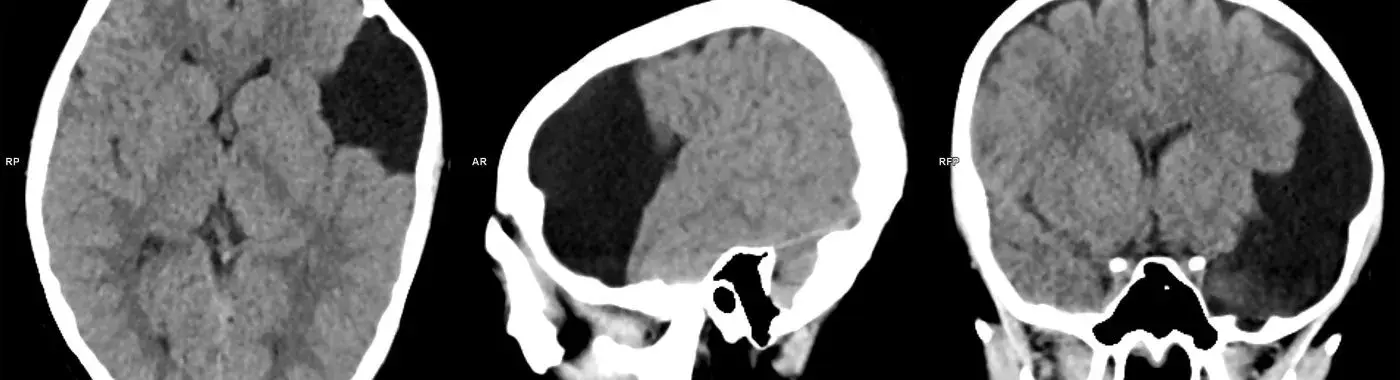

• Imaging Studies: The most common imaging technique used to diagnose arachnoid cysts is magnetic resonance imaging (MRI). MRI provides detailed images of the brain and spinal cord, allowing for accurate identification of cysts. Computed tomography (CT) scans may also be used, particularly in emergency situations.

Arachnoid cysts are benign, fluid-filled sacs located between the arachnoid membrane and the brain or spinal cord. They can vary in size and may be present at birth (congenital) or develop later in life (acquired). These cysts are typically filled with cerebrospinal fluid (CSF) and can occur anywhere in the central nervous system, although they are most commonly found in the temporal lobe of the brain.

Arachnoid cysts are fluid-filled sacs that form in the arachnoid membrane, one of the three layers of tissue that cover the brain and spinal cord. While many individuals with arachnoid cysts may remain asymptomatic, these cysts can sometimes lead to significant neurological issues, making their understanding crucial for both patients and healthcare providers. This article aims to provide a comprehensive overview of arachnoid cysts, including their causes, symptoms, diagnosis, treatment options, and long-term outlook.